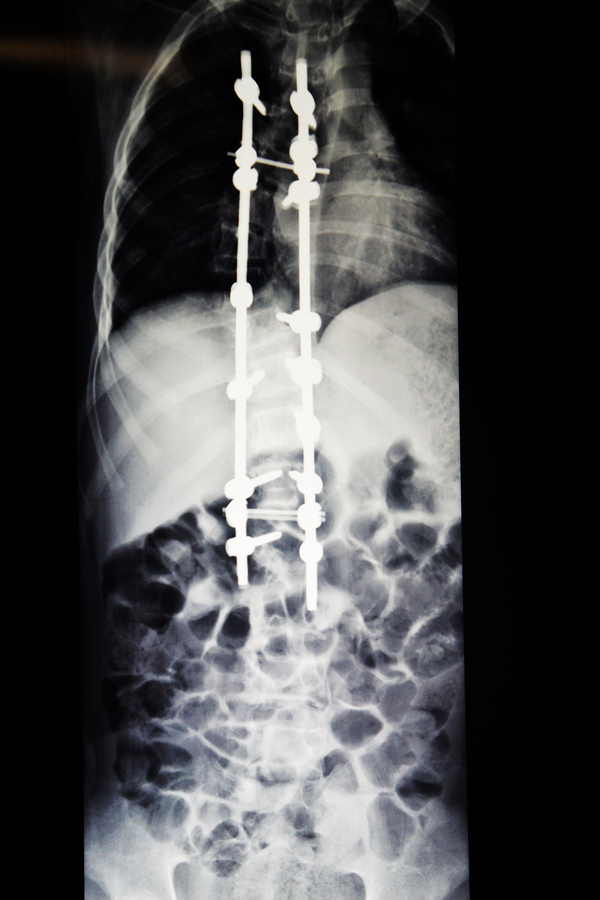

现在,经过手术后的小松脊柱外观基本恢复了正常,他感到背部没有明显的疼痛,且背部的手术伤口也愈合良好,没有发热头晕头痛和恶心呕吐等不适症状,饮食睡眠都很好,四肢感觉、运动、肌力正常。

小松术后的X光片1